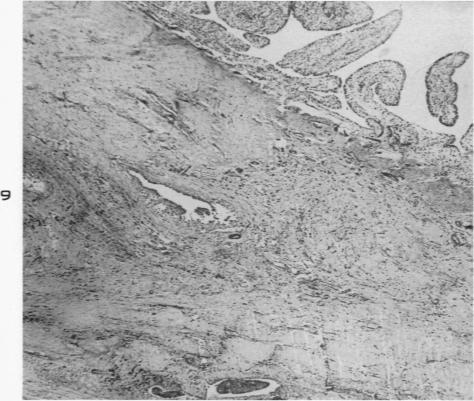

Experimental production of pigmented villonodular synovitis in dogs.

Am J Pathol. 1954 Jul-Aug;30(4):799-811.